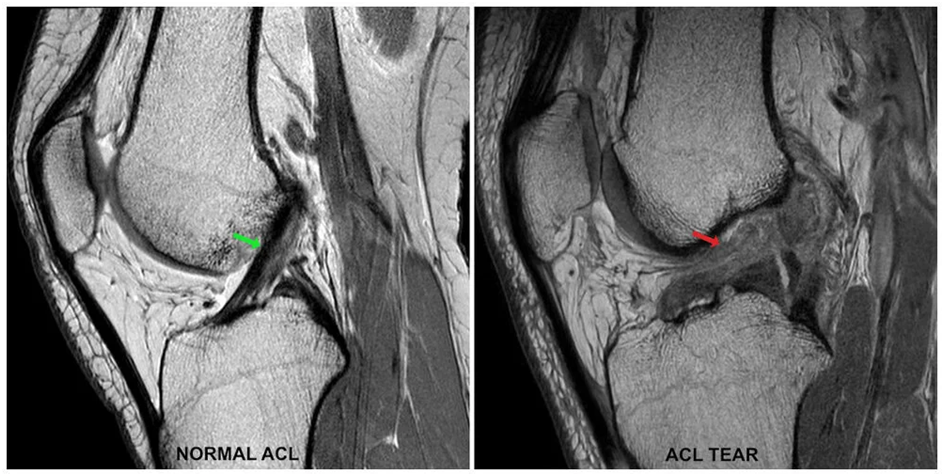

An ACL tear is a common knee injury, especially among athletes. The anterior cruciate ligament (ACL) is one of the key ligaments that helps stabilize the knee joint. A sudden twist, jump, or direct blow can cause the ligament to tear, leading to pain and instability.

If you suspect an ACL tear, consult an orthopedic specialist for the right diagnosis and treatment. Proper care and rehabilitation can help restore knee function and prevent further injury.